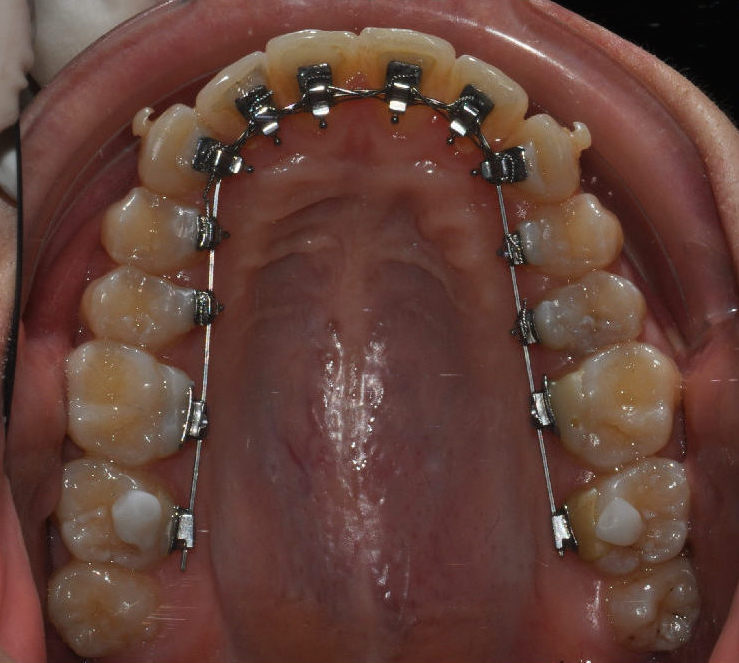

Nel caso della terapia linguale, invece, l’apparecchio viene posizionato sulla superficie interna dei denti.

Anche in questa metodica si sfrutta la tecnologia digitale: gli attacchi, che compongono l’apparecchiatura, vengono prima collocati su modelli virtuali 3D e poi trasferiti sulla dentatura del paziente.